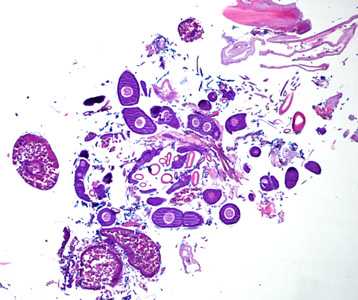

A 70-year-old female, who had recently returned from a trip to Madagascar, went to the hospital for a painful sensation on the underside of her left foot while walking. Examination of the area between the hallux and index toes revealed an ulcerative lesion. A biopsy was performed and sent to the Pathology Department for work-up. The specimen was sectioned, stained with hematoxylin and eosin (H&E) and examined by the attending pathologist. Figures A and B show what was observed at 40x magnification. Figures C and D show the same fields at 200x magnification, respectively. What is your diagnosis? Based on what criteria?

This was a case of tungiasis caused by the chigoe flea, Tunga penetrans. Diagnostic features included:

- location of the parasite between the toes.

- remnants of a sclerotized, chitinous exoskeleton (CU, Figure C).

- remnants of the trachea (TR, Figure C).

- developing eggs (EG, Figure D).